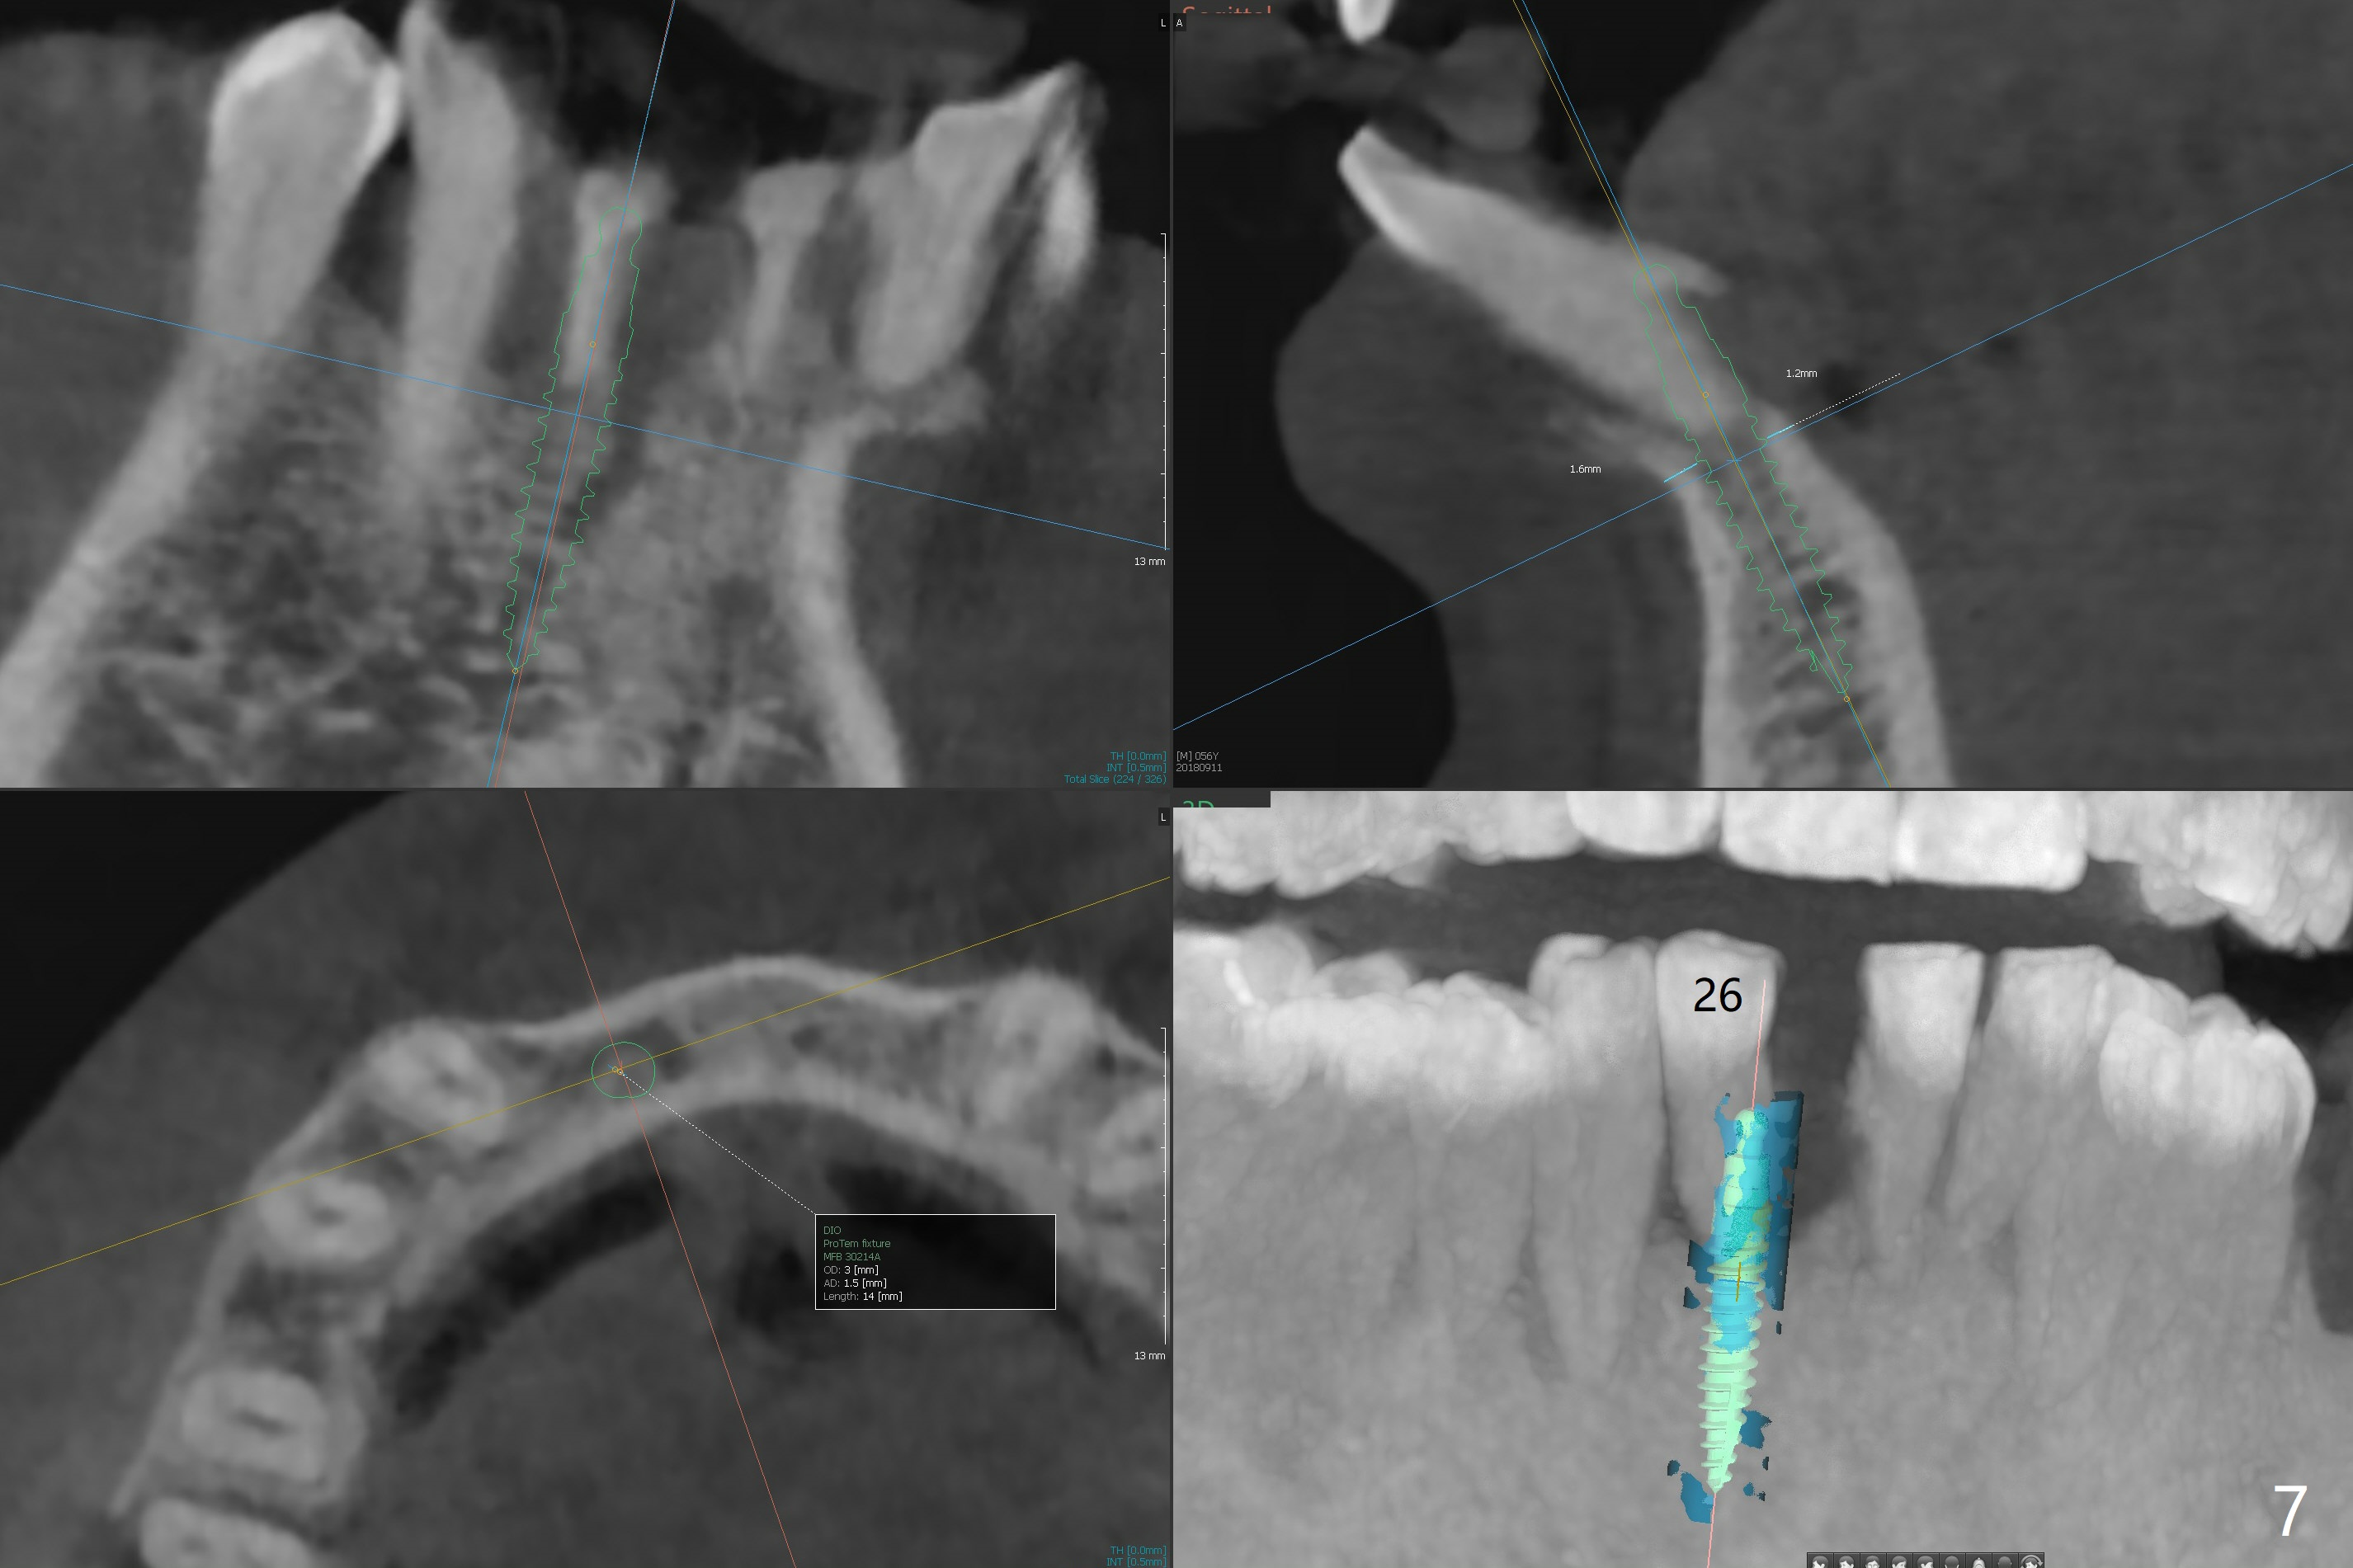

A 56-year-old man is a dental phobic. He finally seeks treatment because of loss of the tooth #25 with air leakage during speech (Fig.1). If the remaining lower incisors are stable after scaling and root planing, a 2.5 or 2.0 mm 1-piece implant will be placed in the narrow edentulous space (Fig.2). The implant driver (green sleeve) may touch the neighboring teeth, which need adjustment. If the worst incisor (#26 tender prior to SRP) is deemed to be non-salvageable, a 2.5 mm implant will be placed with a cantilever 2-unit FPD (Fig.3). If the tooth #23 is a survivor, two of 2.5 or 2.0 implants will be placed at #24 and 26 with a subsequent FPD (Fig.4). If the remaining incisors are all questionable in prognosis, two implants will be placed in the ends with a FPD (Fig.5). After SRP, the tooth #26 is less tender; the patient is ok with its extraction, but insists on saving #23 and 24. If 2 implants are to be placed at #25 and 26, they need to be 2 mm in diameter (Fig.6) with risks of injuring the neighboring teeth. It appears that it is more reasonable to have a single implant, slightly larger (2.5 or 3 mm), at #26, with the coronal end slightly mesial (Fig.7) with a cantilever bridge. If the teeth #23 and 24 fail in the future, a normal one will be easily converted.